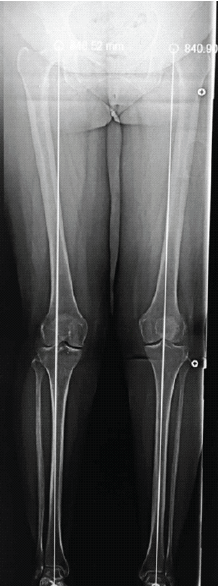

Pre-operative standard knee radiographs were unremarkable, and a scanogram demonstrated normal lower limb alignment (Figs. 1 and 2).

Figure 2: Scannogram showing normal alignment of the lower limb.